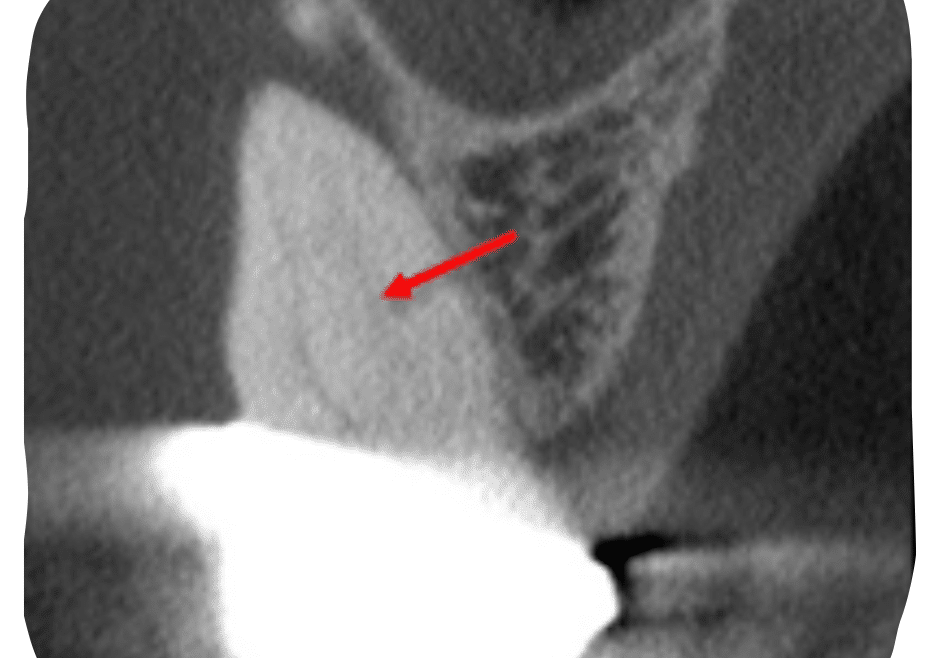

Case Study by Dr. Justin Kolnick

Endoscore of 69 was reduced to a final score of Endoscore 1 after MB2 canal was located and treated.

Obturated with EndoCeramicâ„¢ Sealer (Endo Direct) and single cone gutta percha.

EndoScore: 69 to 1